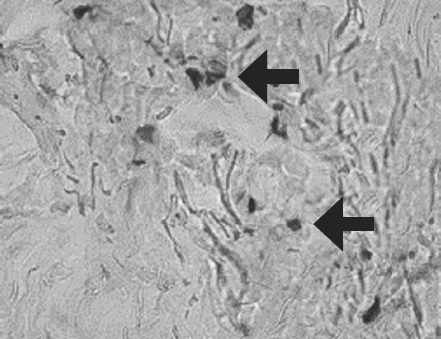

Histological examination of biopsy samples taken from the area of ATMSC transplantation for all the patients revealed the presence of pronounced vascularization with the perifocal proliferation of fibroblasts in both the superficial and deep layers of the dermis (Fig. 6, 7). An immunohistochemical study revealed that the use of ATMSCs resulted in a 5.6-fold increase in the expression of proliferation markers of epithelial and connective tissue cell lines in the injection area (p < 0.01) (proliferation 2.1–2.2), and that apoptotic activity was completely suppressed (Fig. 8, 9). Laser Doppler flowmetry assessment of the microcirculation in the area of stem cell injection on day 7 after early necrectomy, skin grafting, and the administration of MMSCTM showed double the average level of perfusion and mean square deviation of the amplitude of blood flow oscillations than for areas where MMSCTM was not used (p < 0.05) (Table 6).

Fig. 7. Patient E., 49 years old, 5th day of observation. Newly formed vessels with perifocal proliferation of fibroblasts. Color in gof hematoxylin-eosin. Zoom ×400

Рис. 7. Пациент Д., 49 лет, 5-е сутки наблюдения. Новообразованные сосуды с перифокальной пролиферацией фибробластов. Окраска гематоксилином и эозином. Увеличение ×400